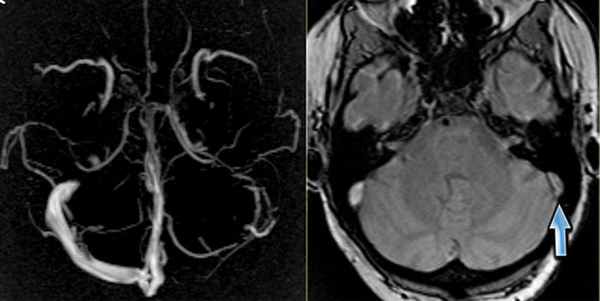

МРТ головного мозга: справа (зеленая стрелка) на Т2-взвешенном изображении отмечается имеющийся в норме феномен «пустоты потока» от правого сигмовидного синуса и яремной Вены. Слева (оранжевая стрелка) отмечается аномально высокий сигнал, в результате, вероятнее, тромбоза. Для подтверждения синус-тромбоза и окончательного определения локализации и протяженности тромбоза необходимо проведение МР-венографии.

МР-венография: тромбоз левого поперечного синуса. Отмечается потеря МР-сигнала от левого поперечного синуса.

Наличие визуализации синуса на «сырых» данных или же МРТ головного мозга подтверждает тромбоз синуса и исключает его гипоплазию.